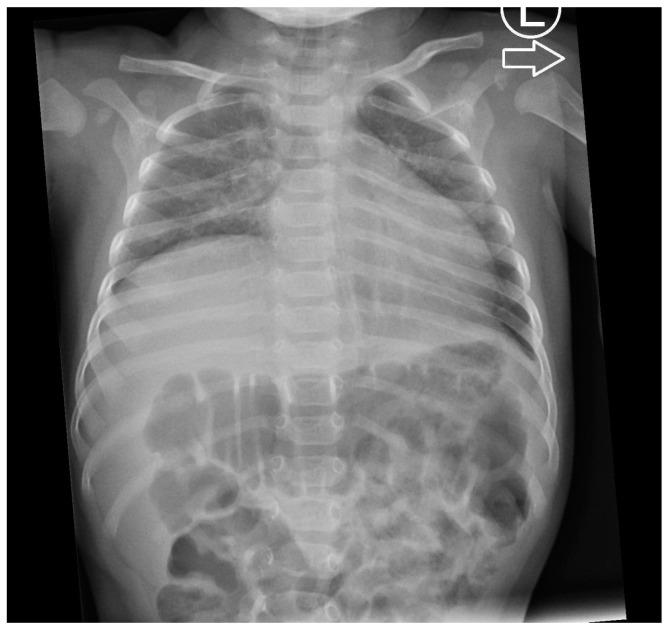

Spinal muscular atrophy with respiratory distress type 1 (SMARD1; OMIM #604320, ORPHA:98920) is a rare autosomal recessive congenital motor neuron disease. It is caused by variants in the gene. Clinically, it presents with respiratory failure due to diaphragmatic paralysis, progressive muscle weakness starting in the distal parts of the limbs, dysphagia, and damage to sensory and autonomic nerves. Unlike spinal muscular atrophy (SMA), SMARD1 has a distinct genetic etiology and is not detected in the population newborn screening programs. Most children with SMARD1 do not survive beyond the first year of life due to progressive respiratory failure. Artificial ventilation can prolong survival, but no specific treatment is available. Therapy focuses on mechanical ventilation and improving the patient's quality of life. Research into gene therapy is ongoing. We report three female patients with SMARD1, including twins from a triplet pregnancy. In twin sisters (patient no. 1 and patient no. 2), two heterozygous variants in the gene were identified: c.595G>C/p.Ala199Pro and c.1615_1623del/p.Ser539_Tyr541del. In patient no. 3, a variant c.1478C>T/p.Thr493Ile and a variant c.439C>T/p.Arg147* in the gene were detected. Our findings underscore the variability of clinical presentations, even among patients sharing the same pathogenic variants in the gene, and emphasize the importance of early genetic diagnosis in patients presenting with respiratory failure, with or without associated diaphragmatic muscle paralysis.

1 型脊髓性肌萎缩伴呼吸窘迫症(SMARD1;OMIM#604320,ORPHA:98920)是一种罕见的常染色体隐性先天性运动神经元疾病。它由 基因的变异引起。临床上,由于膈肌麻痹导致呼吸衰竭,四肢远端逐渐出现肌肉无力、吞咽困难以及感觉和自主神经损伤。与脊髓性肌萎缩症(SMA)不同,SMARD1 具有独特的遗传病因,不在人群新生儿筛查计划中检测到。由于进行性呼吸衰竭,大多数患有 SMARD1 的儿童无法活过一岁。人工通气可以延长生存时间,但没有特定的治疗方法。治疗侧重于机械通气和提高患者的生活质量。基因治疗的研究正在进行中。我们报告了 3 例 SMARD1 女性患者,包括三胞胎妊娠中的双胞胎。在双胞胎姐妹(患者 1 和患者 2)中,鉴定出 基因中的两个杂合变异:c.595G>C/p.Ala199Pro 和 c.1615_1623del/p.Ser539_Tyr541del。在患者 3 中,检测到 基因中的变异 c.1478C>T/p.Thr493Ile 和变异 c.439C>T/p.Arg147*。我们的发现强调了即使在共享相同 基因致病性变异的患者中,临床表现也存在可变性,并强调了在出现呼吸衰竭(伴或不伴相关膈肌肌肉麻痹)的患者中进行早期基因诊断的重要性。